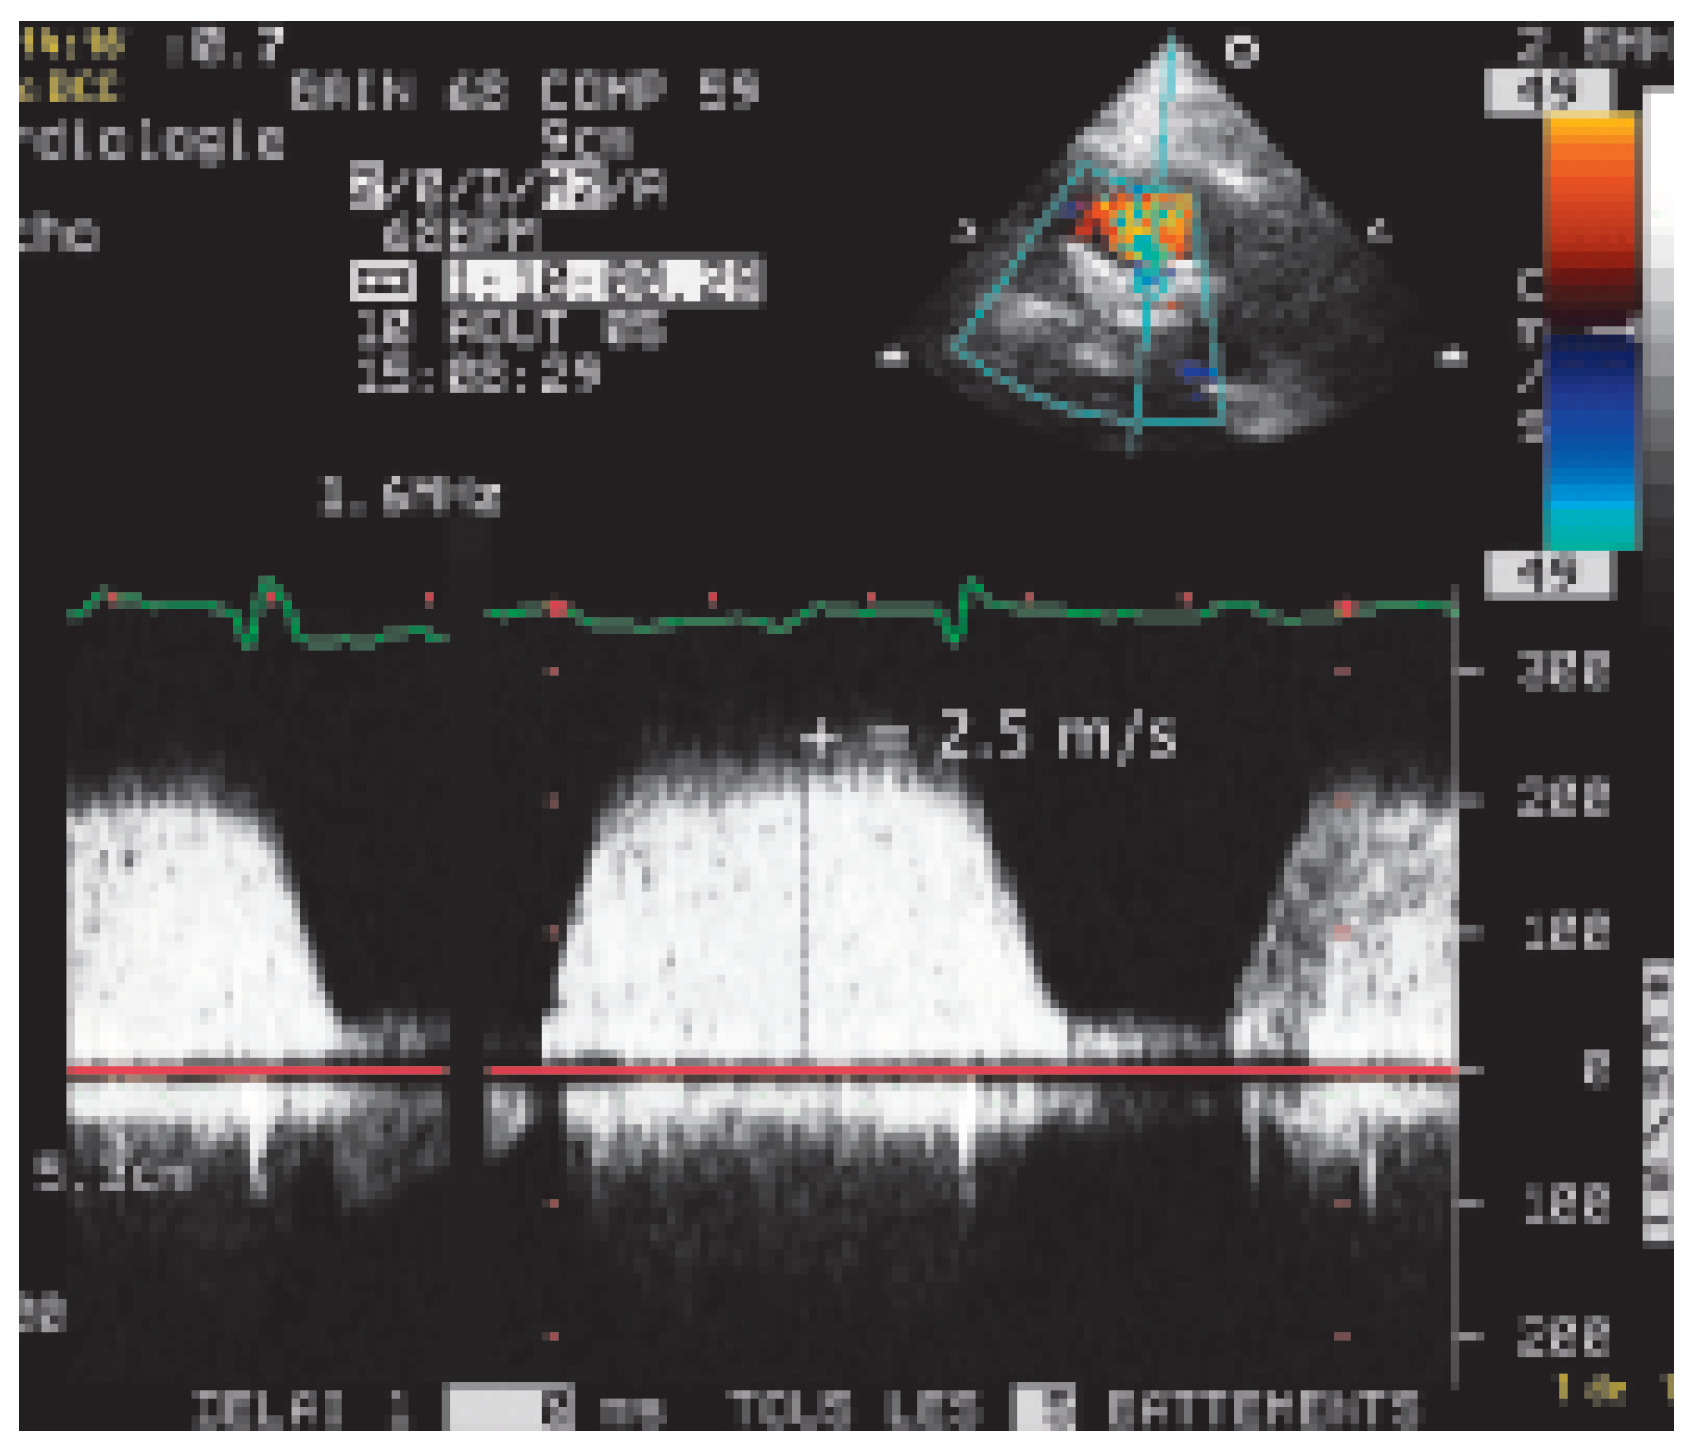

Case report